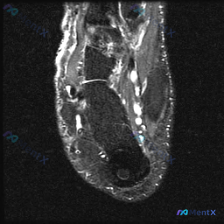

刚整理完一份踝关节MRI(矢状位T2加权序列)的读片资料,挺有启发的,分享一下完整分析思路。 病例影像核心信息 本次分析的影像为踝关节矢状位T2加权MRI,核心发现如下: 1. 骨骼结构:胫骨远端、距骨、跟骨、舟骨等轮廓清晰,未见骨皮质中断、错位,视野内无明显骨髓异常高信号,胫距关节间隙无明显异常,...

刚整理了一份有意思的踝关节MRI病例,初始提示要排查软骨异常,看完片子发现核心问题其实不在这儿,分享一下我的分析思路。 病例基本信息 这是踝关节MRI-T2序列矢状位影像,患者主诉为足跟痛,初始方向锁定为「软骨异常」。 影像学核心发现 1. 骨骼系统:跟骨后下方及足底区域可见不均匀高信号,提示骨髓水...

拿到这张踝关节MRI矢状位T2加权影像,问题提示是「软组织积液」,整理一下完整的读片和分析思路给大家参考。 一、先整理影像基本信息和核心发现 这是一张对比度良好的踝关节矢状位T2加权(大概率脂肪抑制)序列,能清晰看到胫骨远端、距骨、跟骨等主要解剖结构,没有明显伪影。 系统性读片下来的异常发现主要有三...

今天分享一个很有意思的读片病例,问题指向「软骨异常」,但实际影像的核心发现完全不在这个方向,整理一下完整的分析思路和大家讨论。 一、病例影像基础信息 这是一张踝关节MRI矢状位T2加权图像,先给大家整理基本观察结果: 1. 骨骼结构:胫骨远端、距骨、跟骨、舟骨及部分楔骨骨皮质轮廓完整,无明显骨质破坏...

刚整理完一份很有启发的踝关节MRI读片病例,分享给大家,这个病例对临床思维的提醒太到位了。 病例影像基础信息 这是一份踝关节MRI矢状位T2加权图像,临床初始问题是评估是否存在「软骨异常」。 影像核心发现 先给大家说下客观读片结果: 1. 骨骼、软骨情况:胫骨远端、距骨、跟骨等骨质未见明显破坏或水肿...

看到这个踝关节MRI的读片需求,整理一下病例资料和完整分析思路,和大家一起讨论。 病例影像基本信息 这是一张踝关节矢状位T2加权MRI影像,核心发现是存在软组织积液,具体观察结果如下: 1. 骨骼情况:胫骨远端、距骨、跟骨、足舟骨骨皮质完整,没有明显骨折线,也没有广泛骨髓水肿信号 2. 关节情况:胫...

分享一份踝关节矢状位MRI读片病例,整理了分析思路给大家讨论。 一、病例影像基本信息 这是一例踝关节矢状位MRI读片病例,初始观察提示为「软骨异常」,以下是完整影像评估: - 骨骼结构:胫骨远端、距骨、跟骨、舟骨形态完整,骨皮质连续,骨髓信号均匀,无明显骨髓水肿、骨折 - 关节间隙:胫距关节、距下关...